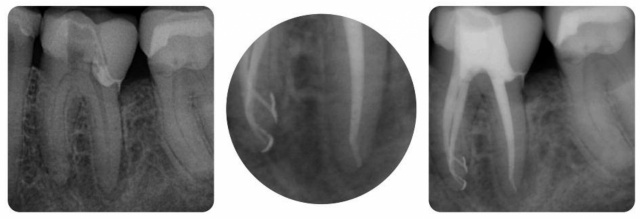

Sehr geehrter Herr Winter,gerne berichte ich über die Erfahrungen mit dem von der Firma Winray gelieferten Röntgencontainer.Als Betreiber einer radiologischen Anlage stellen sich in der…